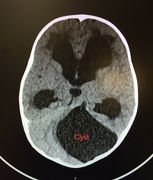

Obstructive hydrocephalus

Ventricles

- Check all 4 for size and for hemorrhage

- Temporal tips (comma-shaped) of lateral ventricle first place to show hydrocephalus

- If enlarged must differentiate between hydrocephalus from increased pressure versus atrophy:

- Are the gyri effaced? If yes suggestive of increased pressure